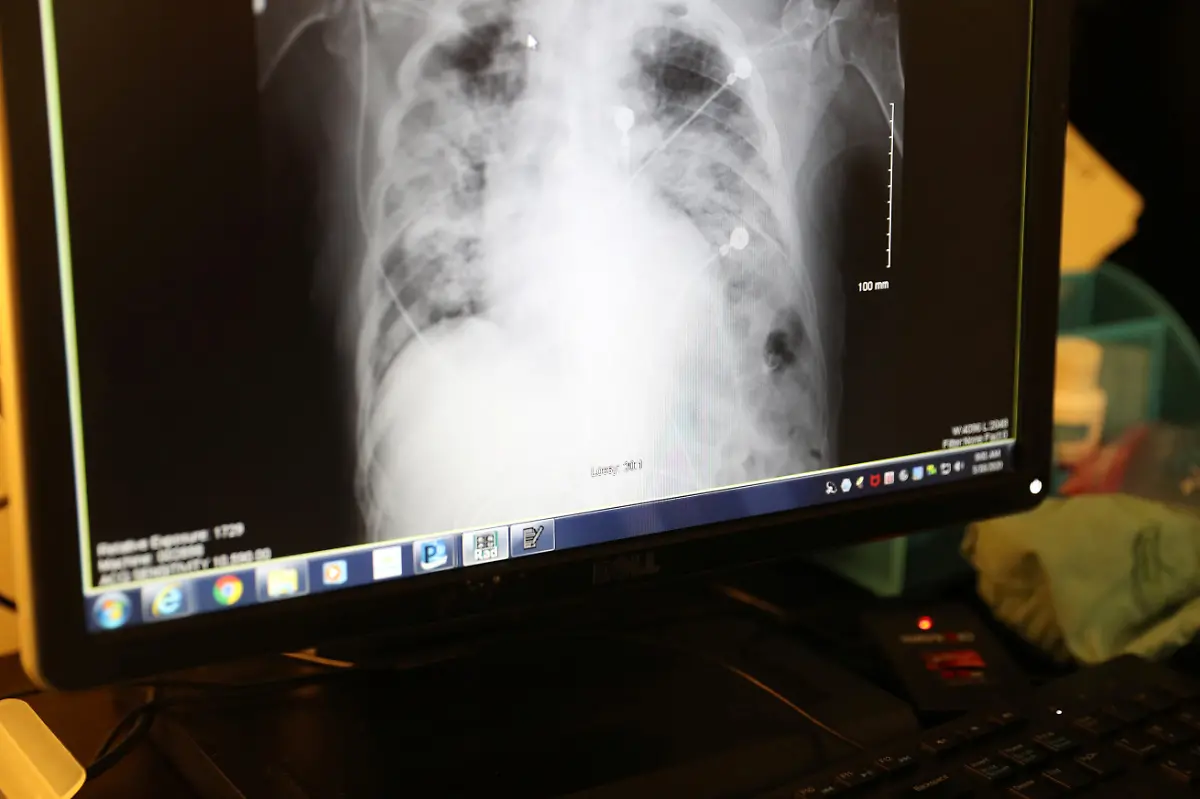

Die Patienten von Dr. Zafia Anklesaria stammen aus den ärmsten Vierteln von Los Angeles. Hier greift das Coronavirus besonders schnell um sich, die Sterberaten sind höher als bei den Wolhabenden. Anklesaria erwartet in Kürze ihr erstes Kind und ist dennoch bei ihren Patienten.